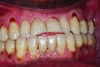

A rotten egg or cabbage smell is indicative of VSC being the main cause of halitosis. These compounds are usually associated with periodontal disease (Figure 3 and Figure 4) and/or tongue coating. Patients suffering from periodontitis or peri-implantitis require professional periodontal treatment in order to eliminate periodontal pathogens.5 Following a professional scaling and root planing appointment, Gram-negative anaerobic bacteria responsible for causing periodontal disease and producing VSC are reduced.5 This, in turn, encourages repopulation with Gram-positive cocci and bacterial rods that are associated with oral health.

Evaluation of the patient’s full mouth series of radiographs revealed signs of mild periodontal bone loss and a large carious lesion/defective restoration on tooth No. 19. A treatment plan was devised that included oral hygiene instructions, scaling/root planing, root canal treatment on No. 19, crown fabrication on No. 19, and re-evaluation 4 to 6 weeks later. During the re-evaluation appointment, oral hygiene was shown to be slightly improved, and a 3-month periodontal maintenance interval was suggested (Figure 8). The patient reported a significantly decreased degree of malodor and was very satisfied.